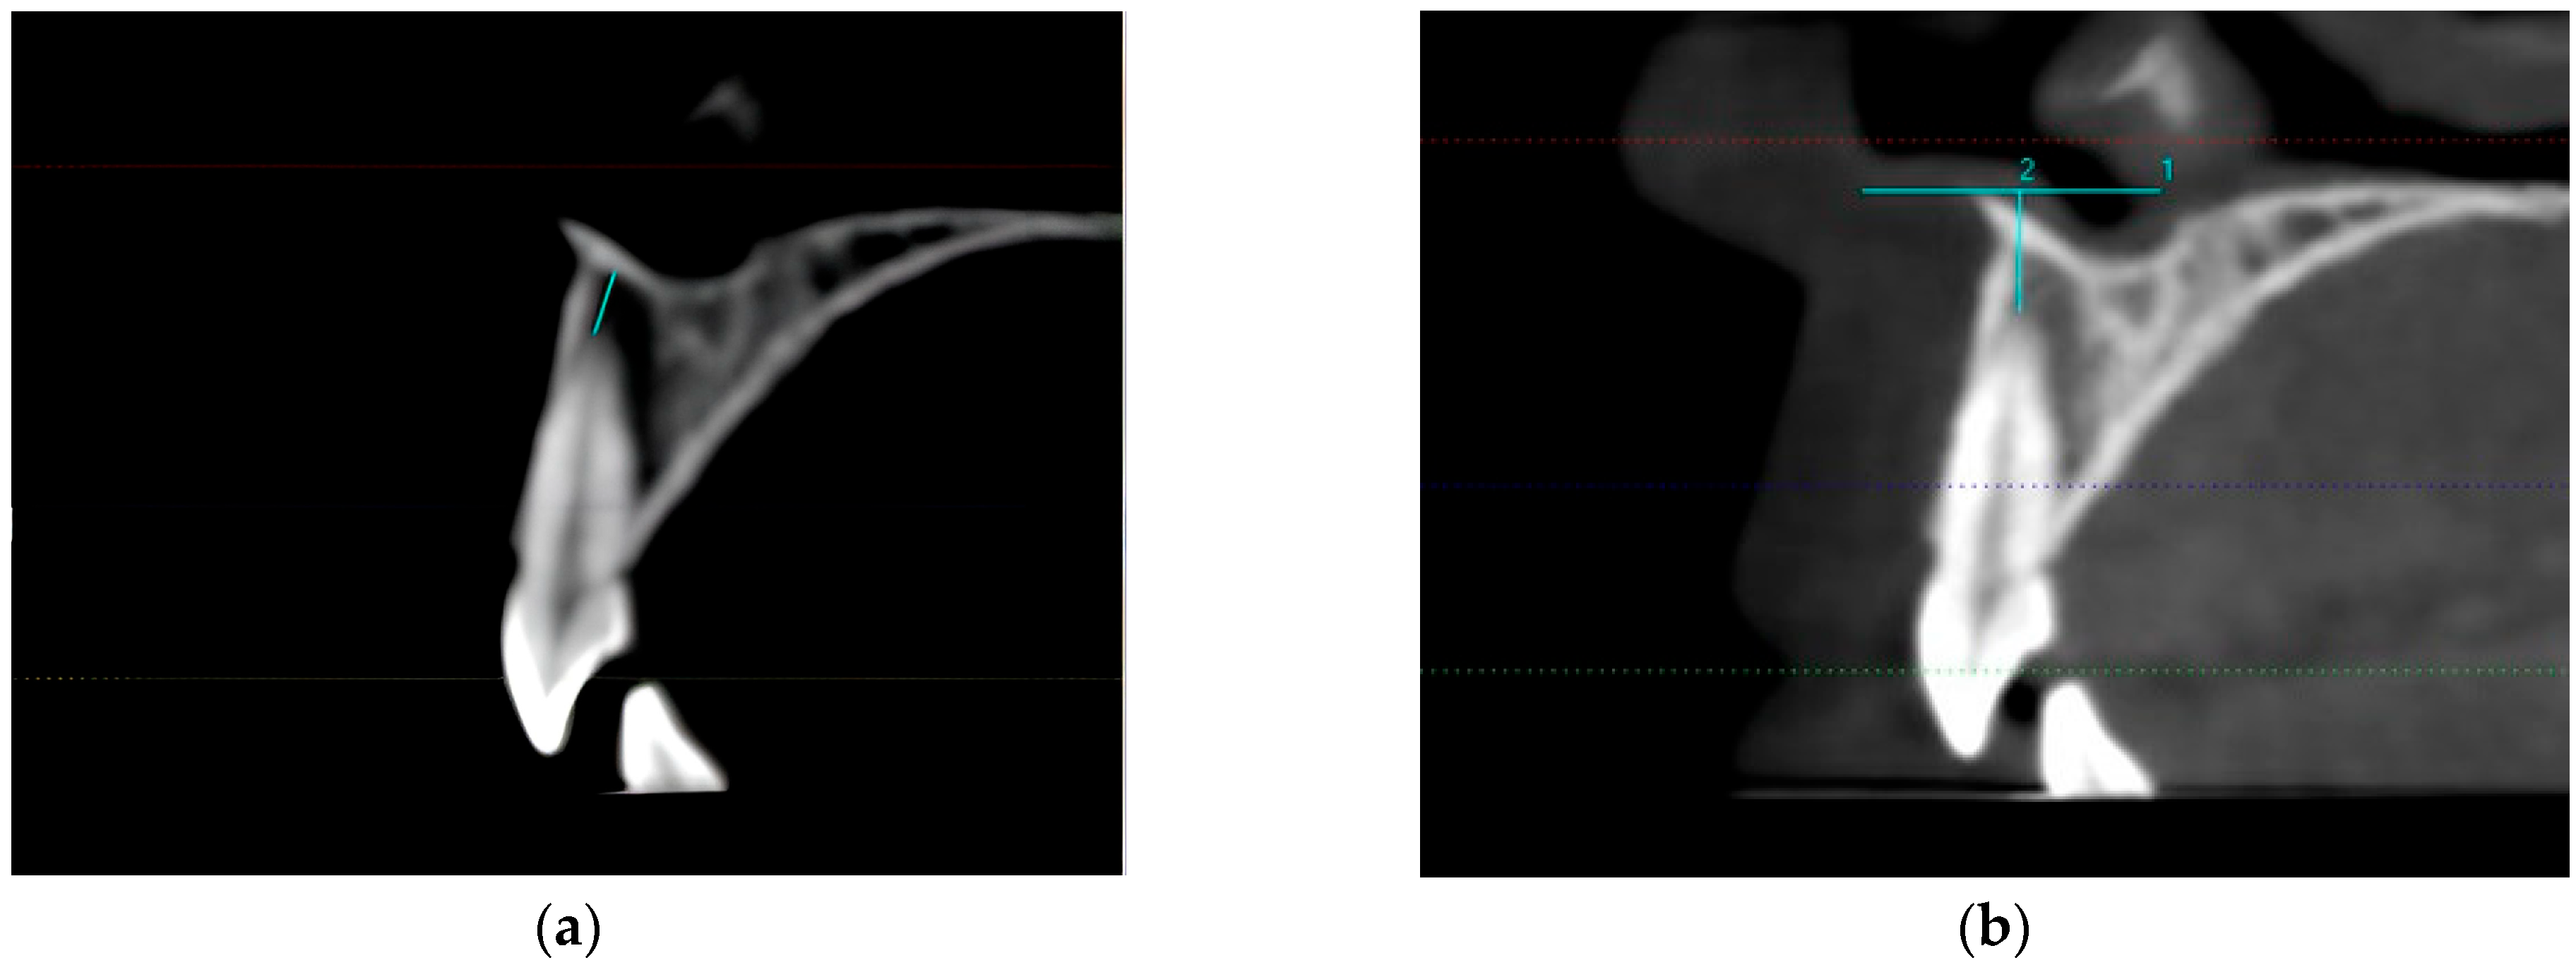

2.2. CBCT Measurements